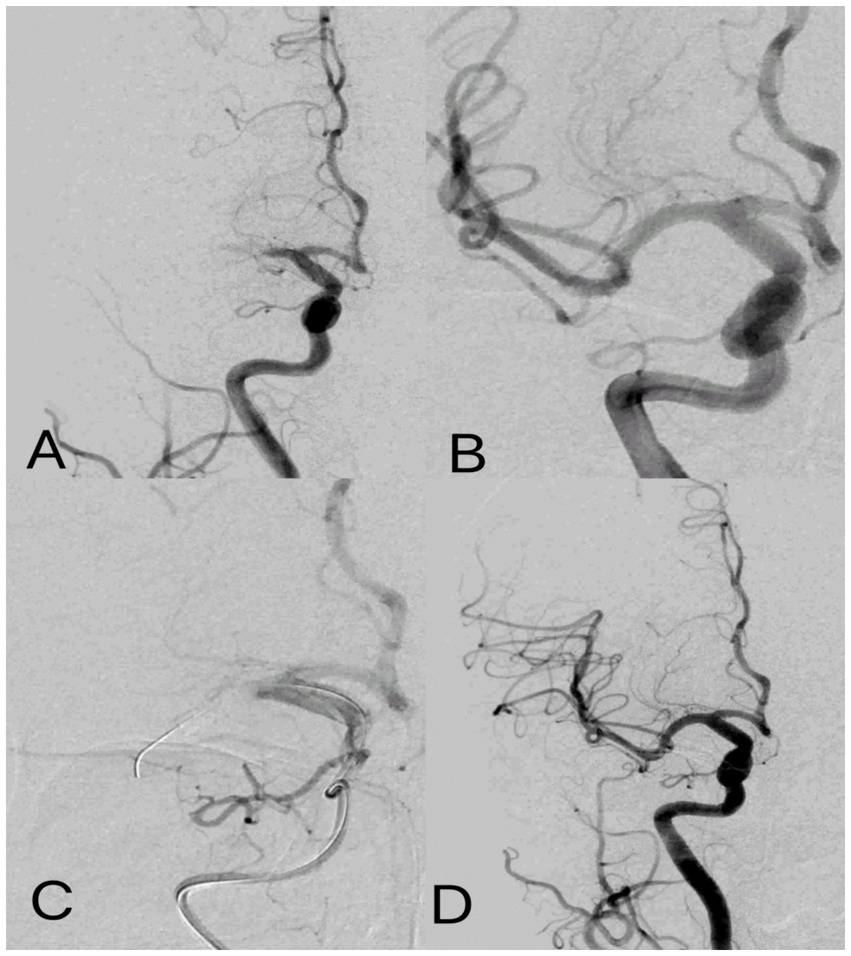

Figure 2

Post-ischemic conditioning of middle cerebral artery occlusion. Digital subtraction angiography: (A) occlusion of the M1 segment of the middle cerebral artery. (B) cerebral artery thrombectomy was completed, and the middle cerebral artery was fully open. (C) For IPC, the balloon was placed at the occlusion site to induce temporary occlusion, and angiography showed complete occlusion of the middle cerebral artery with no blood flow passing through. (D) IPC was completed with flow patterns consistent with those after cerebral artery thrombectomy.